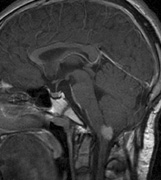

Optic pathway gliomas arise from the astrocytes of the optic nerve. Most are pilocytic astrocytomas and typically remain intradural, extending in the subdural space. Malignant transformation is rare. There appear to be two growth patterns62:

- Perineural growth pattern, correlating with a diagnosis of NF1. The tumor expands in the subarachnoid

space and the optic nerve is compressed as a central ribbon. On

T2-weighted MRI, this may be seen as a low-intensity core with surrounding

high-intensity rim. Increased tortuosity of the optic nerve is also

associated with this growth pattern (Fig. 5).63

- Intraneural growth pattern, correlating with the absence of NF1.

The incidence of optic pathway gliomas in NF1 is difficult to estimate, as the majority are asymptomatic and do not affect vision. In NF1, radiographic evidence of an optic nerve glioma occurs in 15% of patients.64,65 Most tumors are neither suspected historically nor detected by ophthalmic examination.65 Even when optic nerve gliomas become clinically detectable, visual function often remains stable in the absence of any intervention.66,67 Thus routine computed tomography (CT) imaging, even in patients with a known optic nerve glioma, is controversial. The potential risks of repeated radiation exposure in a child with a tumor-suppressor gene defect is a consideration. MRI studies are more revealing than CT but may require sedation or anesthetic and are costly. An MRI is often recommended at the time of diagnosis, but in most cases routine “follow-up” MRIs are unnecessary. Annual ophthalmic clinical examination for relative afferent pupillary defect (RAPD), visual acuity, visual fields, color vision, and funduscopy is usually all that is required, as no therapeutic action is likely to be taken unless there is significant and progressive visual involvement.

Optic nerve gliomas may involve the optic chiasm and be associated with endocrine disorders or nystagmus.68–70 Surgical excision of chiasmal gliomas (Fig. 6) carries a high risk of visual loss. Invasion of the hypothalamus or the third ventricle carries a poor prognosis, with greater than 50% 15-year mortality rate.71 One review of radiation treatment for chiasmal gliomas collated data from small case series and found no significant long-term improvement in visual function, progression, or mortality with radiation treatment.71 Other reports suggest that radiation doses over 4500cGy improve symptoms and slow progression of chiasmal gliomas over several years.72 Adequate tumor coverage by radiotherapy results in irradiation of normal brain and nearly all children need hormone replacement.73 Chemotherapy is an alternative.74,75